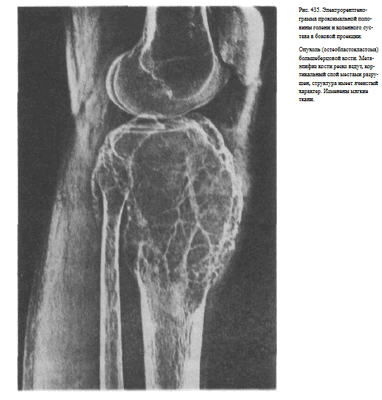

Информативность снимка. На рентгенограмме видны обе берцовые кости, их диафизы и метаэпифизы. В области диафизов костей хорошо различаются мозговая полость и корковое вещество. На снимках проксимальных двух третей голени, выполненных на пленке размером 24 х 30 см, отображены головка малоберцовой кости, частично или полностью метаэпифиз большеберцовой кости, а также иногда рентгеновская суставная щель коленного сустава (рис. 430, а). На снимках дистальных двух третей голени выявляются дистальные метаэпифизы большеберцовой и малоберцовой костей, иногда медиальная и латеральная лодыжки и рентгеновская суставная щель голеностопного сустава (рис. 430, б).

На снимке проксимальных двух третей голени (на пленке размером 24 х 30 см) раздельно определяются диафизы берцовых костей, а проксимальные метаэпифизы наслаиваются друг на друга. Видна бугристость большеберцовой кости (рис, 433, а).

На снимке дистальных двух третей голени также диафизы костей видны раздельно, а изображение метаэпифиза малоберцовой кости полностью суммируется с изображением метаэпифиза большеберцовой кости и таранной костью. Видна рентгеновская суставная щель голеностопного сустава